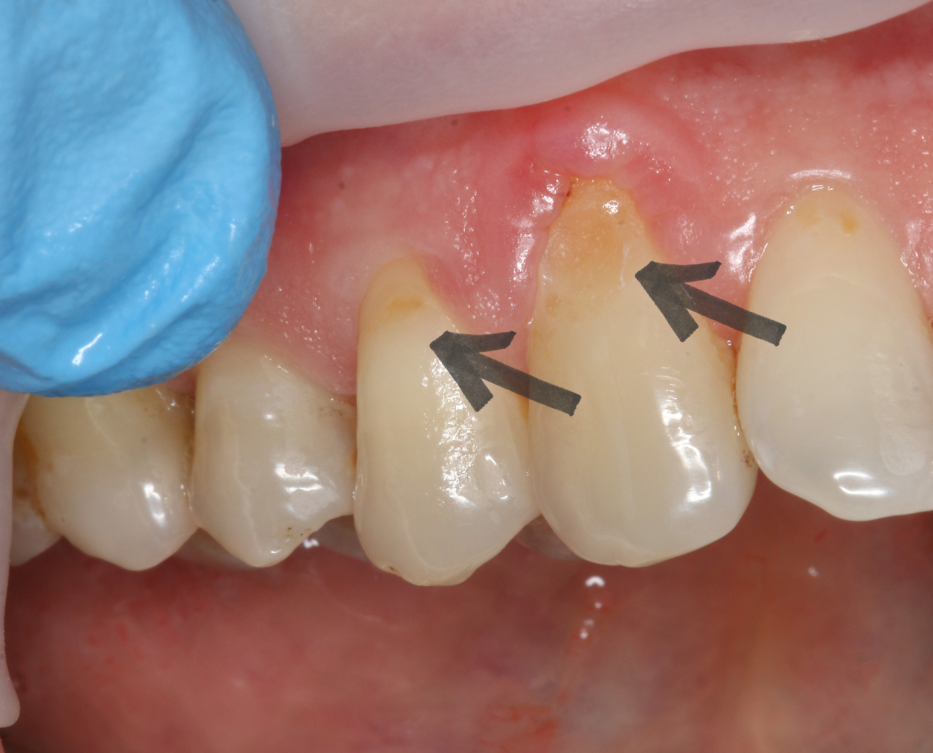

Пример клиновидных зубов

Клиновидный дефект — это не кариес и не скол. Это некариозное поражение зуба. Он выглядит как небольшая выемка в области шейки зуба (то есть у самой десны). Если посмотреть сбоку, она действительно напоминает клин, отсюда и название.